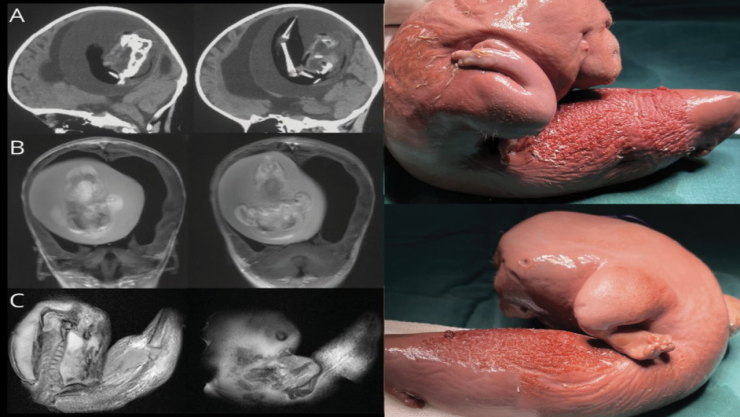

Esto ocurrió en China, las autoridades de la Universidad de Fundan en Shangái, realizaron una intervención quirúrgica a una niña de un año de edad que tenía alojado el feto de su hermano gemelo en el cerebro.

Esta situación considerada como anomalía tiene como nombre"fetus in feto” (feto en feto) o "gemelo parásito” siendo inusual en el mundo; la última vez que ocurrió un caso similar, los reportes fueron publicados en la Revista Neurology en diciembre del 2022.

El extraño parásito fue retirado del cerebro de la menor de edad, la masa de carne extirpada era un feto "malformado"; el cual se alojaban en el cerebro, sitio donde representaba un riesgo para la pequeña.

Aunque, ambos bebés fueron se encontraban en la misma placenta pero tenían sacos amnióticos diferentes, sin embargo, en algún punto del crecimiento el feto no nacido se incrustó en el cerebro de la niña.

En la historia de la humanidad solos se han documentado 200 casos similares, de los cuales solo 28 se alojó el feto en el cráneo del individuo nacido, siendo más común que el "parásito" se aloje en el vientre. El bebé no nacido desarrollo la columna vertebral, dos huesos de la pierna, así como también un par de dedos en sus extremidades superiores.

Los padres se dieron cuenta de lo que le sucedía a su hija debido a que presentaba retraso en su habilidades motoras, lo que hizo que fuera revisada por los médicos descubriendo que se encontraba creciendo su hermano no nacido en su cerebro, por lo cual tuvo que ser intervenida; a su vez los científicos mencionaron que este siguió creciendo debido al suministro de sangre.